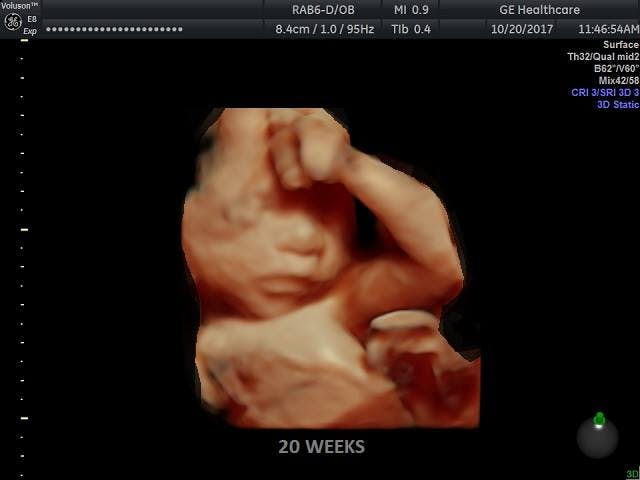

Sen. Lindsey Graham (R-SC) asked one of the majority witnesses, Dr. Colleen A. Malloy, Assistant Professor of Pediatrics-Neonatology at Northwestern University Feinberg School of Medicine, if it would be standard practice in neonatal surgery to give a 20 or 22-week-old baby anesthesia. Malloy testified that in neonatal and fetal surgery the baby would be administered anesthesia “because they can feel pain.”